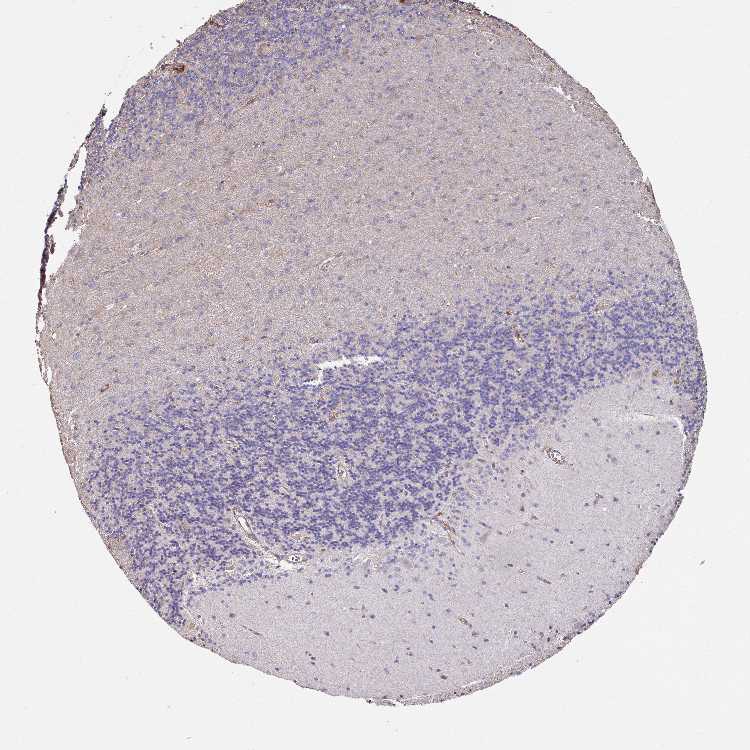

BRAIN CEREBELLUM Show tissue menu

CEREBELLUM - Expression summary

CEREBELLUM - Antibody stainingi

Antibody staining in the annotated cell types in the current human tissue is reported as not detected, low, medium, or high, based on conventional immunohistochemistry profiling in selected tissues. This score is based on the combination of the staining intensity and fraction of stained cells.

Each image is clickable and will lead to virtual microscopy that enables deeper exploration of all samples and also displays staining intensity scores, fraction scores and subcellular localization as well as patient and tissue information for each sample.

Antibody HPA039948

Purkinje cells Low

Cells in granular layer Low

Cells in molecular layer Low